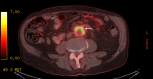

Aortic graft infection